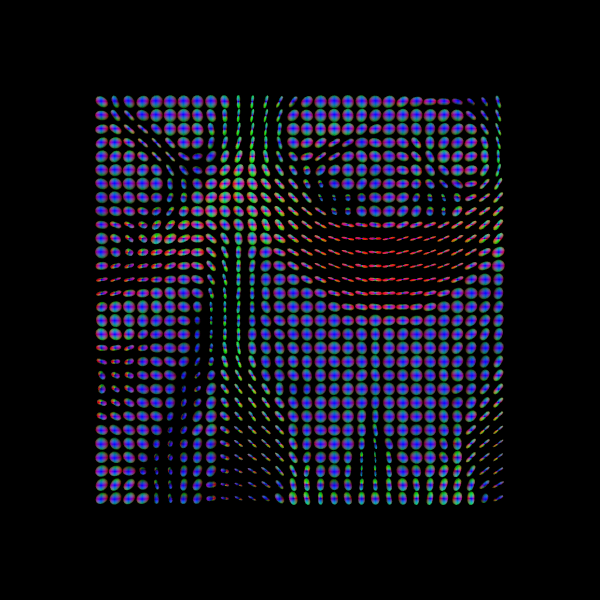

We can also find the peak directions (maxima) of the ODFs with peaks_from_model.

scene = window.Scene()

scene.add(

actor.peak_slicer(

peaks_csd.peak_dirs[20:50, 55:85, 38:39], peaks_values=peaks_csd.peak_values[20:50, 55:85, 38:39],

colors=None,

)

window.record(scene=scene, out_path="csd_direction_field.png", size=(600, 600))

Image("csd_direction_field.png")

../_images/e0431602bb8df52f997a45c7b57ac89b59c64a0c4d37c0bfbe360dd212068884.png

We now visualize both the ODFs and peaks in the same space.

fodf_spheres.GetProperty().SetOpacity(0.4)

scene.add(fodf_spheres)

window.record(scene=scene, out_path="csd_both.png", size=(600, 600))

Image("csd_both.png")

../_images/9074060ddb34e03025e6ef30e9b7d968c7fd48464caf8bdb1f35c0b11e2fad26.png